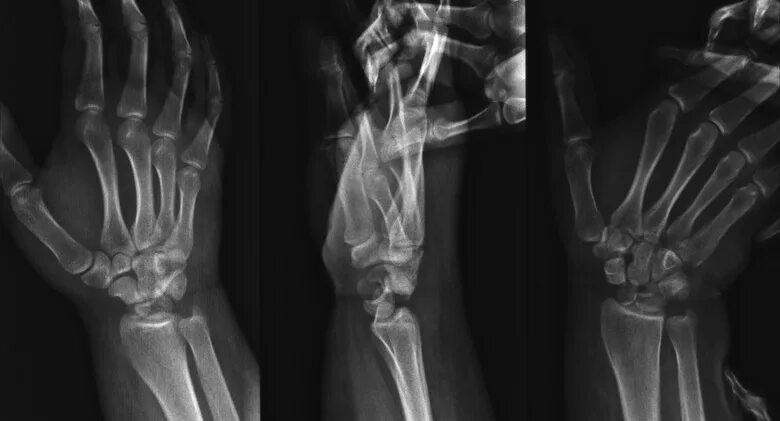

Перелом лучезапястного сустава лечение